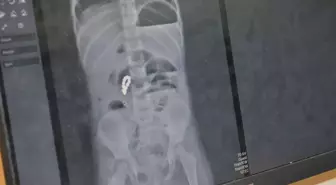

- 4 yaşındaki Eda'nın bağırsağından 8 adet mıknatıslı boncuk çıkarıldı